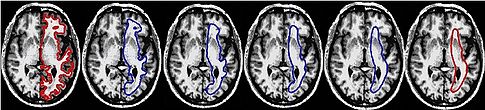

Joint Segmentation of Image Ensembles via Latent Atlases Three cross-sections of 3D segmentations of Hippocampus, Amygdala and Superior Temporal Gyrus in the left and right hemispheres. Automatic segmentation is shown in red. Manual segmentation is shown in blue. Fourth column: Coronal views of the resulting atlases for each pair of structures. Read more...

Cortical Correspondence with Probabilistic Fiber Connectivity. Brain deflation progress for one subject. The surface outline is shown in con- trasting colors overlayed on an axial slice of the brain. The leftmost image shows the original WM surface, and the consequent images show the progress of the deflation at 1000 iteration intervals. The second rightmost surface is used for retrieving proba- bilistic connectivity images after a final scaling step, shown on the far right. Note the progressive smoothing of the gyri as the surrounding regions become flat, which relaxes the velocity constraint on these vertices. Read more...